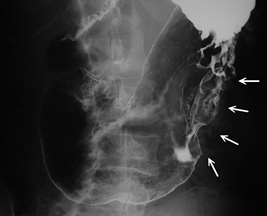

2:注腸検査

注腸といわれる検査です。肛門から10cmほど管を入れて、管を 通してバリウムと空気を注入し、大腸全体を細かくX線で撮影します大腸に便が残っていると検査の精度が落ちてしまいますから、事前に下剤投与などの前処置が必要です。検査自体つらいという患者さんは皆無ですが、下剤による腹痛や頻回の排便が大変だったという声は比較的多く耳にします。一日で大腸の中を空っぽにしようとするのですから多少の腹痛は我慢するしかありませんが、個人差もあり、夜中に何度も「腹痛→排便」という方もいるようです。医療に携わるものとしては、より負担の少ない下剤の開発かまたはそれに代わる方法が開発されることを切に望みます。検査前日の食事は検査食と言われ、レトルト食品や粉末飲料など一日分がセットになって販売されています。この市販の検査食にはいろいろな種類がありますが,

いわゆる大腸癌検診として行われている便潜血反応が陽性の場合、次に行われる検査はこの検査になります。

←画面中央に直腸癌が認められる